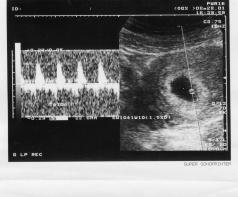

我那時產檢

醫生是跟我說

照到的小黑點是胚囊

胚囊裡有一個小白點是胚胎

也就是之後心臟跳動的點

我那時看的書是說,第一次超音波照到著床的圓圓的東西就是胚囊,

然後有了心跳以後才是胚胎,懷孕兩個月以後因為已經有了人類的基本雛形才叫做胎兒。